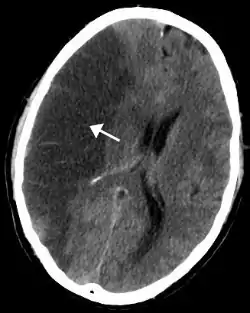

الجلطة الدماغية النزيفية

- الأشعة المقطعية (بدون تحسينات على النقيض)

حساسية = 89٪ خصوصية = 100

بالنسبة للسكتات الدماغية النزفية، قد يكون التصوير المقطعي أو التصوير بالرنين المغناطيسي مع تباين داخل الأوعية قادرًا على تحديد الشذوذ في شرايين الدماغ (مثل تمدد الأوعية الدموية) أو مصادر أخرى للنزيف، والتصوير بالرنين المغناطيسي الهيكلي إذا لم يظهر هذا أي سبب. إذا لم يحدد هذا أيضًا سببًا أساسيًا للنزيف، فيمكن إجراء تصوير الأوعية الدماغية، لكن هذا يتطلب الوصول إلى مجرى الدم عن طريق قسطرة داخل الأوعية ويمكن أن يسبب المزيد من السكتات الدماغية بالإضافة إلى مضاعفات في موقع الإدخال وبالتالي يتم إجراء هذا التحقيق ل حالات محددة.[57] إذا كانت هناك أعراض توحي بأن النزف ربما حدث نتيجة للتخثر الوريدي، يمكن استخدام تصوير الأوردة المقطعية أو التصوير بالرنين المغناطيسي لفحص الأوردة الدماغية.[57]